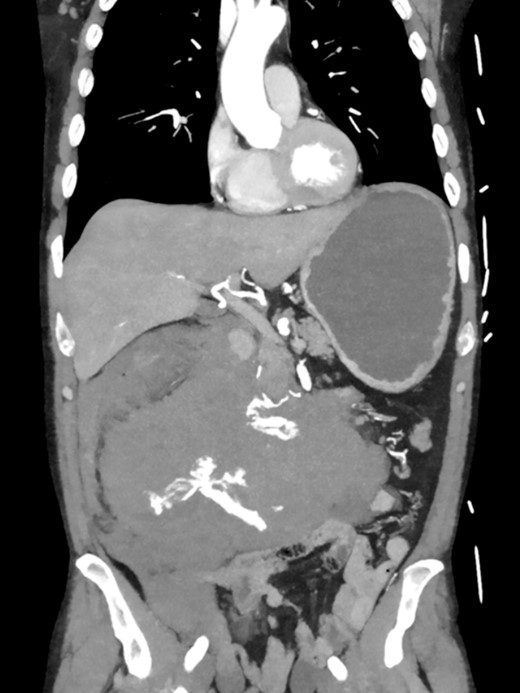

Postoperatively, the patient achieved hemodynamic stabilization in the intensive care unit. On the sixth postoperative day, there was a recurrence of circulatory collapse in addition to relevant bloody discharge through the drains. CT imaging once again revealed an active bleeding of the pancreaticoduodenal artery, which was successfully treated interventionally using coiling (Figs 2 and 3).

Postinterventional angiography, showing the aneurysm of the pancreaticoduodenal arcade, after interventional coiling.